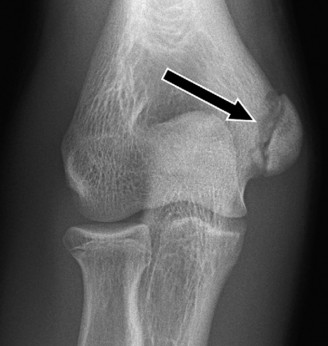

CASE 40 A 16-year-old male baseball player presents to your office for evaluation of his worsening right elbow pain. He denies acute injury or inciting event. The pain is located on the posteromedial aspect of his elbow and is exacerbated by throwing. It has been present for the past 6 months, but it has been more severe over the past 3 months.

On examination, he has tenderness to palpation over his olecranon and pain with terminal elbow extension. He has no evidence of varus or valgus instability. No pain with resisted wrist flexion. His images are shown (Figs. 2–108 to 2–110).

Figure 2–108

The correct answer is (A). This syndrome occurs most commonly in competitive pitchers, with pain that is worse in the deceleration phase and at terminal extension. The resulting chronic stress results in chondrolysis, osteophyte formation, and attenuation of the MCL. Medial epicondylitis is also common in pitchers, but the pathology is limited to the flexor pronator mass. Pain is over the medial epicondyle and is worse with wrist and forearm flexion. OCD lesions are most common in the capitellum, often present with mechanical symptoms. Olecranon stress fractures result from repetitive abutment into the olecranon fossa. This is a plausible answer, however, the MRI findings are not consistent. MCL rupture is typically acute and is not seen on the MRI shown.